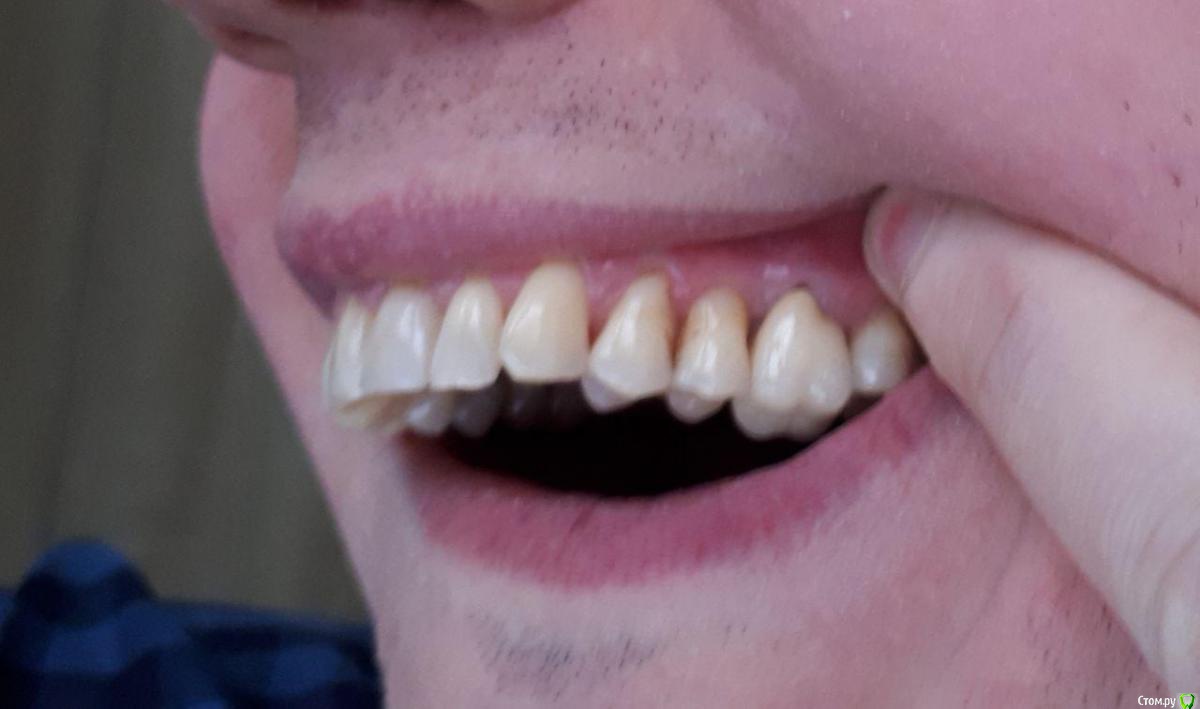

Доброго времени суток! Будьте добры, посоветуйте хорошего, опытного хирурга-пародонтолога, работающего поближе к Магнитогорску.- Челябинск, Екатеринбург, Уфа, Оренбург, Самара, который смог бы помочь мне с моей проблемой,а проблема заключается в генерализованной рецессии. Заранее Спасибо!